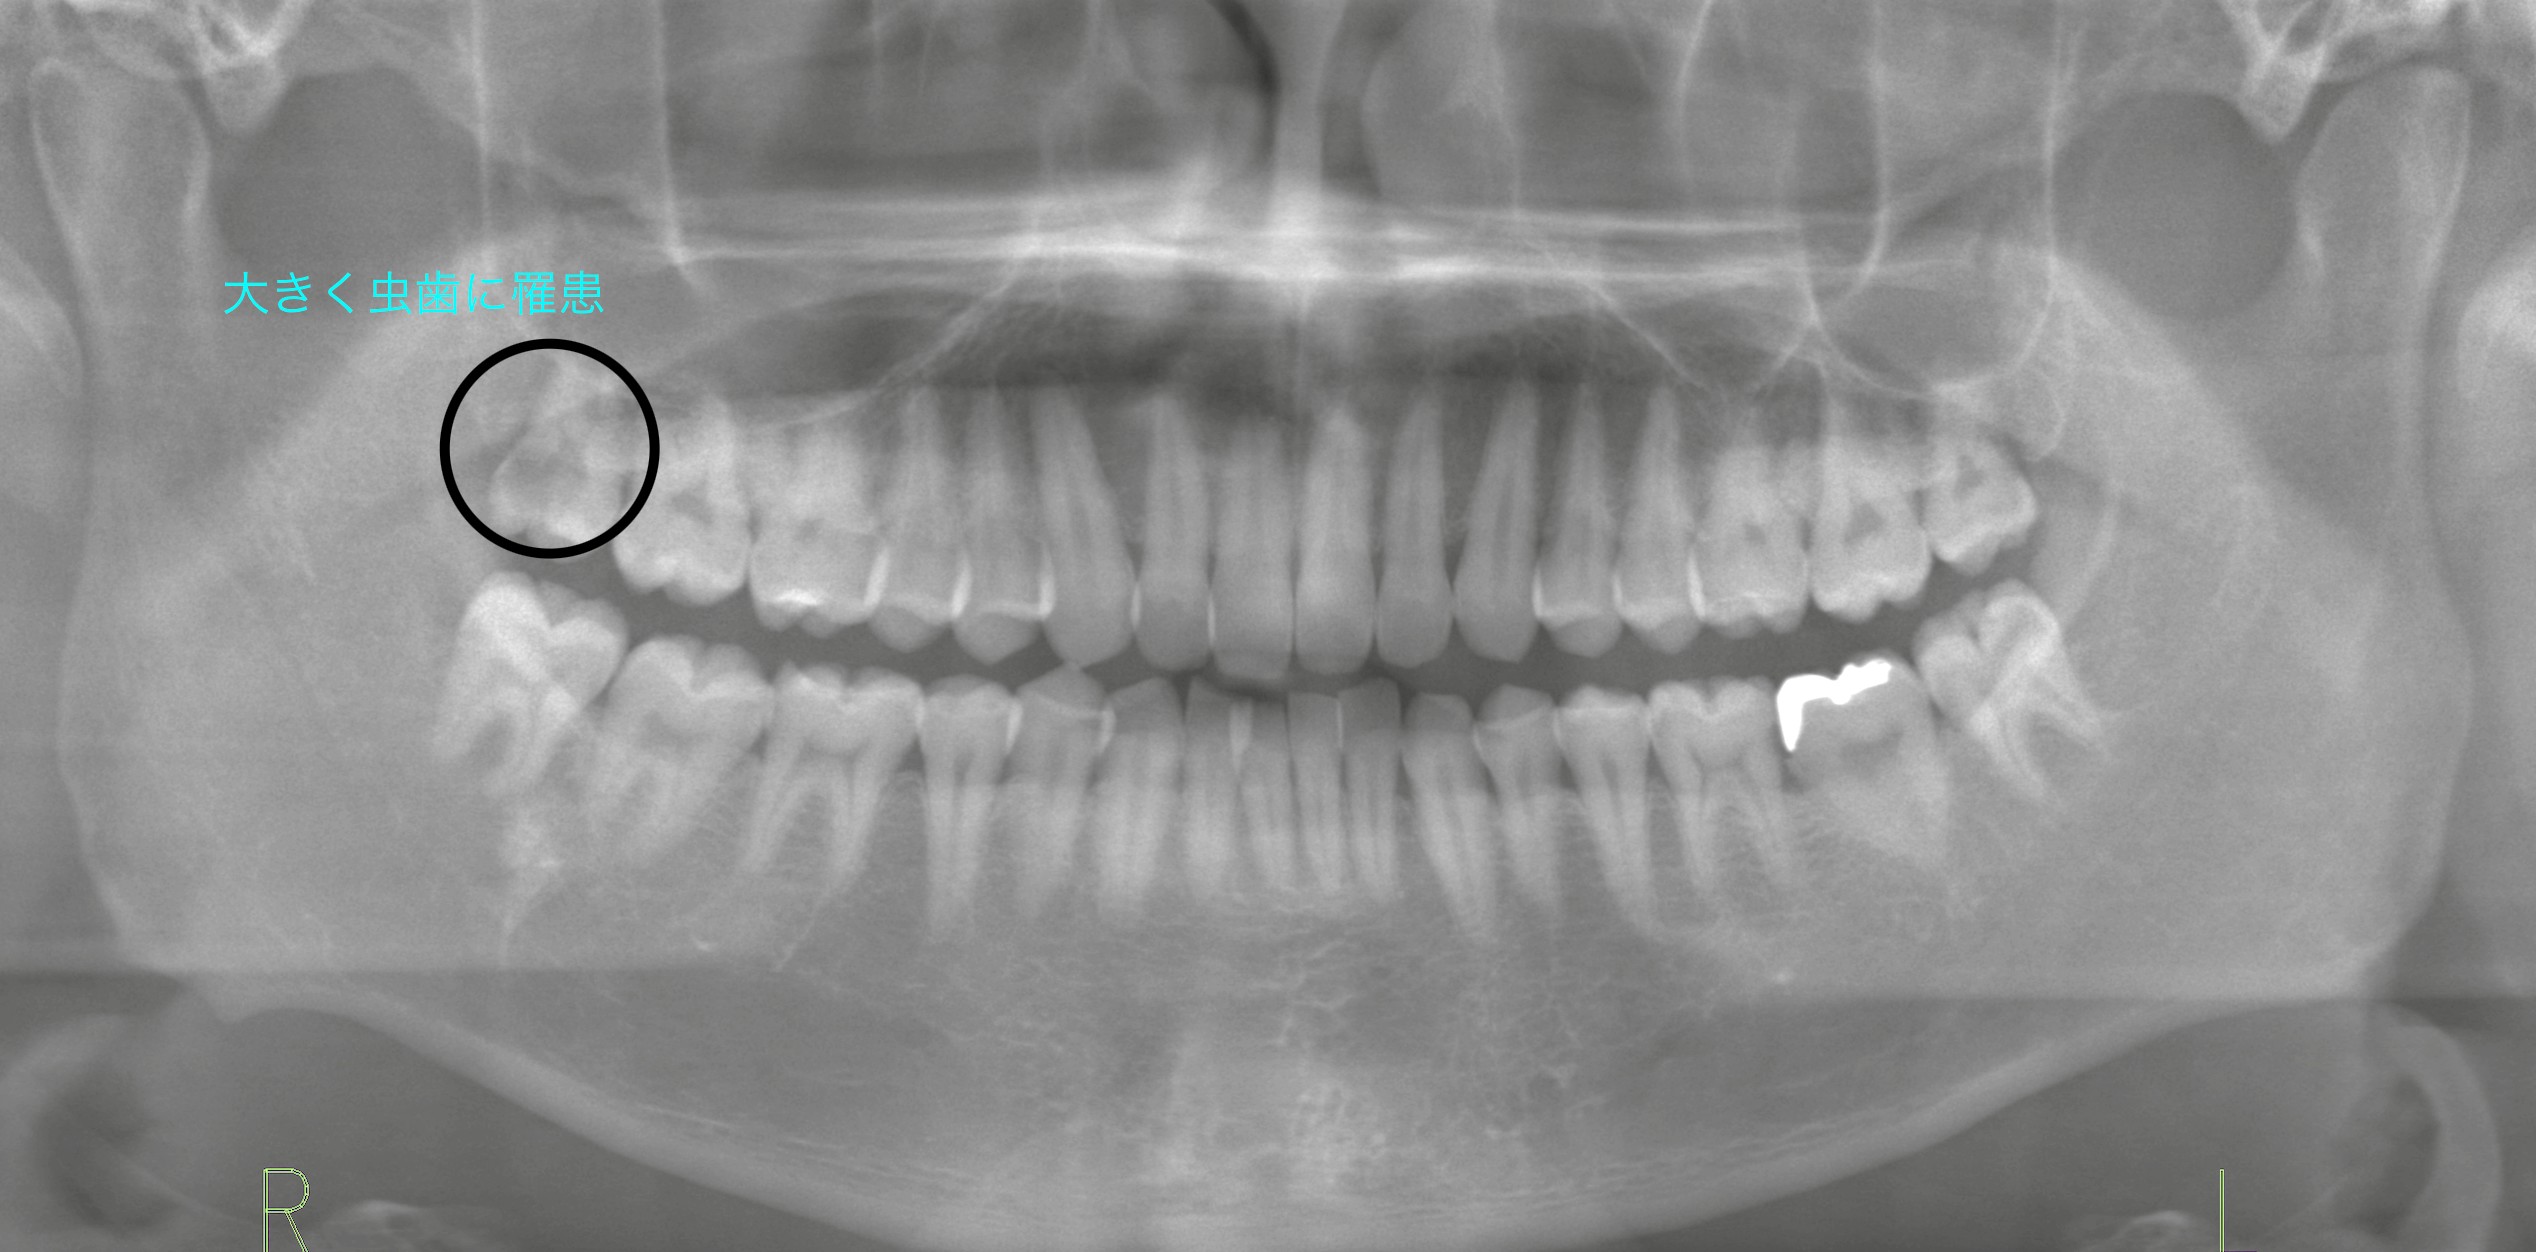

診査を行うと、原因は右上の親知らずにできた大きな虫歯でした。レントゲン撮影にて確認すると、虫歯はすでに神経(歯髄)まで到達している状態でした。また、対合する親知らずとの間にはわずかながら咬合関係も認められました。

今回の症例では、右上の親知らずが神経まで達する大きな虫歯を起こし、強い痛みの原因となっていました。治療の困難さと再発リスクを考慮し、抜歯によって口腔全体の健康を守るという結論に至りました。